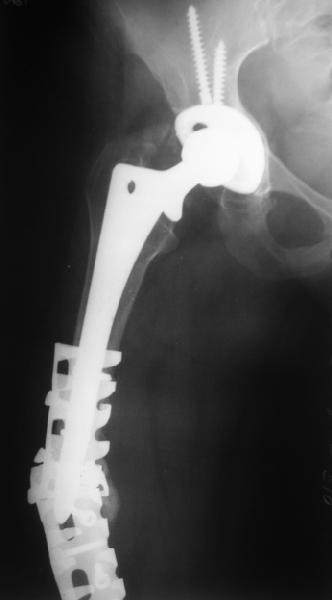

Спасибо за обсуждение. После нескольких дней тракции аппаратом сделали. Попытка закрытой репозиции не удалась из-за смещения по ширине, мешали фрагменты цемента. После их удаления репозиция получилась. Еще убрали немного цемента с ножки по латерльной стороне, чтобы обнажить 40-50 мм ее дистальной части, для плотной посадки гвоздя. Дальнейшее введение гвоздя было несложным. Протез показался нам стабильным в проксимальной части как латерально, так и медиально. Картинки в приложении.

THX for the discussion. After few days of traction by ex-fix the surgery was performed. An attempt of closed nailing was unsuccesful because of fragment translation, which was blocked by cement fragments. After removal of broken cement pieces reduction was reached "automagically". Also some cement from lateral part was removed by

chisel to expose distal 40-50 mm of the stem to allow tight fit of the nail. Further fixation by the nail was pretty easy and straightforward. Images attached. The stem looked stable in its proximal part both laterally and medially. Comments/critics are welcome.